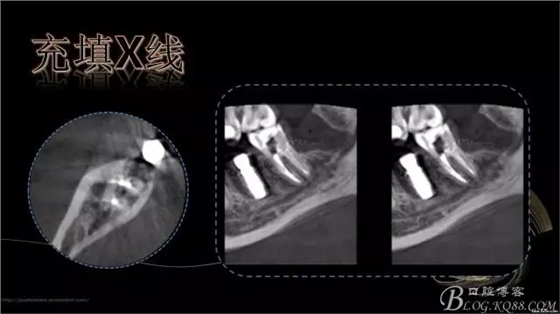

640.webp (6).jpg

640.webp (7).jpg